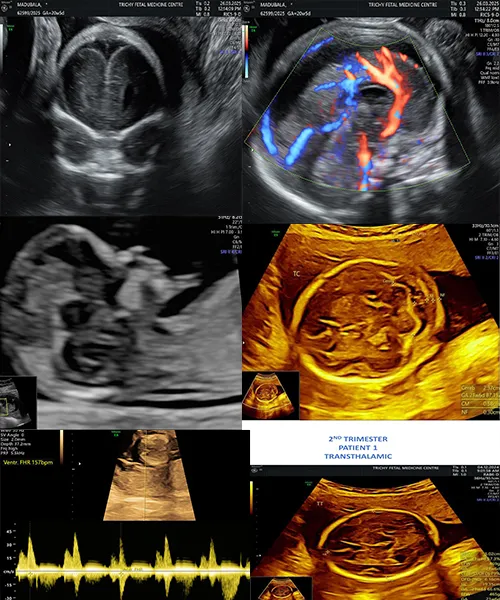

Fetal Neurosonogram

Growth Scan with Doppler